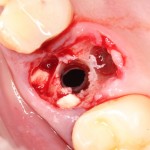

Синуслифтинг: что делать при перфорации слизистой оболочки гайморовой пазухи?